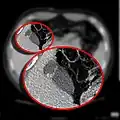

CT scan showing a phrygian cap

In medicine, a Phrygian cap is the folded portion of some gallbladders that resembles the Phrygian cap (a soft conical cap with the top pulled forward, associated in antiquity with the inhabitants of Phrygia, a region of central Anatolia). It is a normal anatomical variant seen in 1-6% of patients.[1] It is caused by a fold in the gallbladder where the gallbladder fundus joins the gallbladder body.[2] Apart from the chance of being mistaken for stones on a sonogram, it has no other medical implications nor does it predispose one to other diseases. However, due to potential decrease in bile flow, it may warrant a preventive removal of the gallbladder.